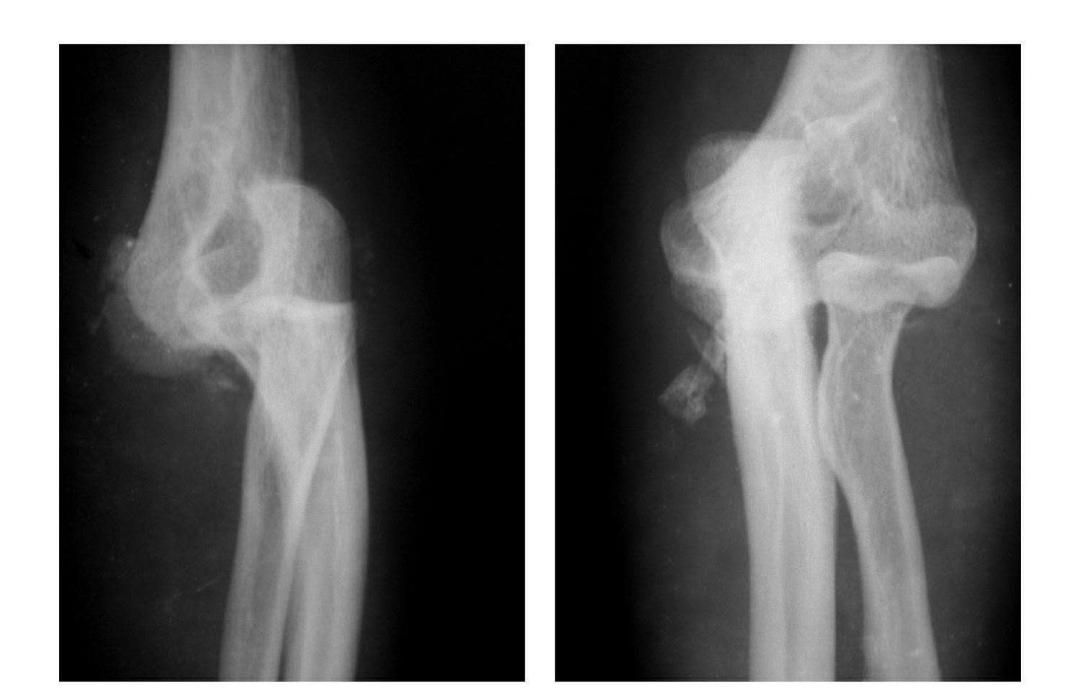

肱骨小头矢状面骨折

本病文献未见报道,即肱骨小头中部呈前后(矢状面)纵向骨折,将小头分为内外两部分。

本病因有明显的外伤史,即健侧小头正常,从而排除了先天因素。

例:肱骨小头矢状面骨折,折线波及外髁皮质骨折片,并鹰嘴突无移位骨折。